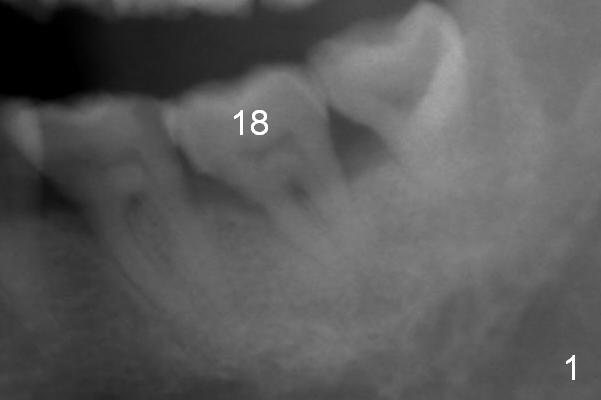

A 59-year-old man has history of chronic periodontitis (Fig.1 (taken in 2005), 2 (2014), 3 (2016)) involving the tooth #18. The bone loss may be complicated by bruxism. Large crown vs. narrow roots contributes to severe bone loss. An implant should be as long as possible and placed as coronally as possible to tackle crown/implant ratio issue. To prevent peri-implantitis, the implant may have to be placed deep. It appears that the bone height is more favorable mesially than distally (Fig.3). After extraction of the supraerupted and loose tooth (Fig.4; no Antibiotic), explore the socket to determine the favorite osteotomy site, most likely the mesial socket, lingually.